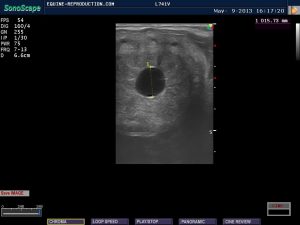

Growth of the embryonic vesicle between days 10-17 is usually linear, averaging approximately 3.4 mm/day. In order to maintain a constant, the images below between days 10-18 are all of the same mare’s pregnancy. There is a slight “bump” in the linearity on day 14, but the overall average is maintained. A temporary plateau of growth and final cessation of mobility within the uterus commences around day 17. This plateau of cross-sectional conceptus diameter, showing only a marginal increase of diameter, if any at all, will continue until around day 28 by which time the yolk sac (of which the early vesicle primarily consists) is regressing in size, while the allantoic sac is increasing in diameter. Although the uterine horn cross-sectional diameter remains constant, the conceptus is in fact undergoing longitudinal elongation up the uterine horn, which can be visualised by placing the transducer in a longitudinally along the uterine horn.

Note that on each of the images from day 10-15 there appears at both the top and the bottom of the conceptus a small white area. This is thought by some to be a definitive indication that this is a pregnancy rather than a cyst or other fluid-filled area of the uterus, but that is incorrect. The small white area doesn’t even physically exist! It is called a spectral reflection and is an artefact of ultrasonography which may be seen on any enclosed area of fluid being ultrasounded.

Around day 17 – often exactly to the day – a loss of regularity of shape of the vesicle occurs in conjunction with cessation of movement through the uterus. This is primarily as a result of the conceptus increasing in diameter to a point greater than the internal diameter of the uterine horns. This cessation of movement is often erroneously referred to as “implantation”, but there is no invasion of the endometrium (the uterine lining) at this stage, and the correct term is “fixation”. The loss of regularity of shape has been seen to be a cause of concern by some – even to the point of belief of impending pregnancy loss and treatment with prostaglandin to “start again” – but it is absolutely normal at this stage. Concern is sometimes compounded by the belief that the mare is a few days earlier post-ovulation than she truly is, the duration calculation having been made from the time she was last positively responsive to the stallion. Following estrus, mares do not become resistant to a stallion until progesterone levels are adequately elevated to cause that resistance, and the progesterone source is the developing Corpus Luteum (“CL”) which forms following ovulation. Resistance to the stallion may therefore not occur until as much as 48 hours after ovulation, although up to 24 hours is more common. When viewing mare ultrasound pregnancy images calculated as being 15 days from that point could therefore mean she is in reality as much as 17 days post-ovulation and conception – and in the time frame when loss of regularity of shape is to be expected.